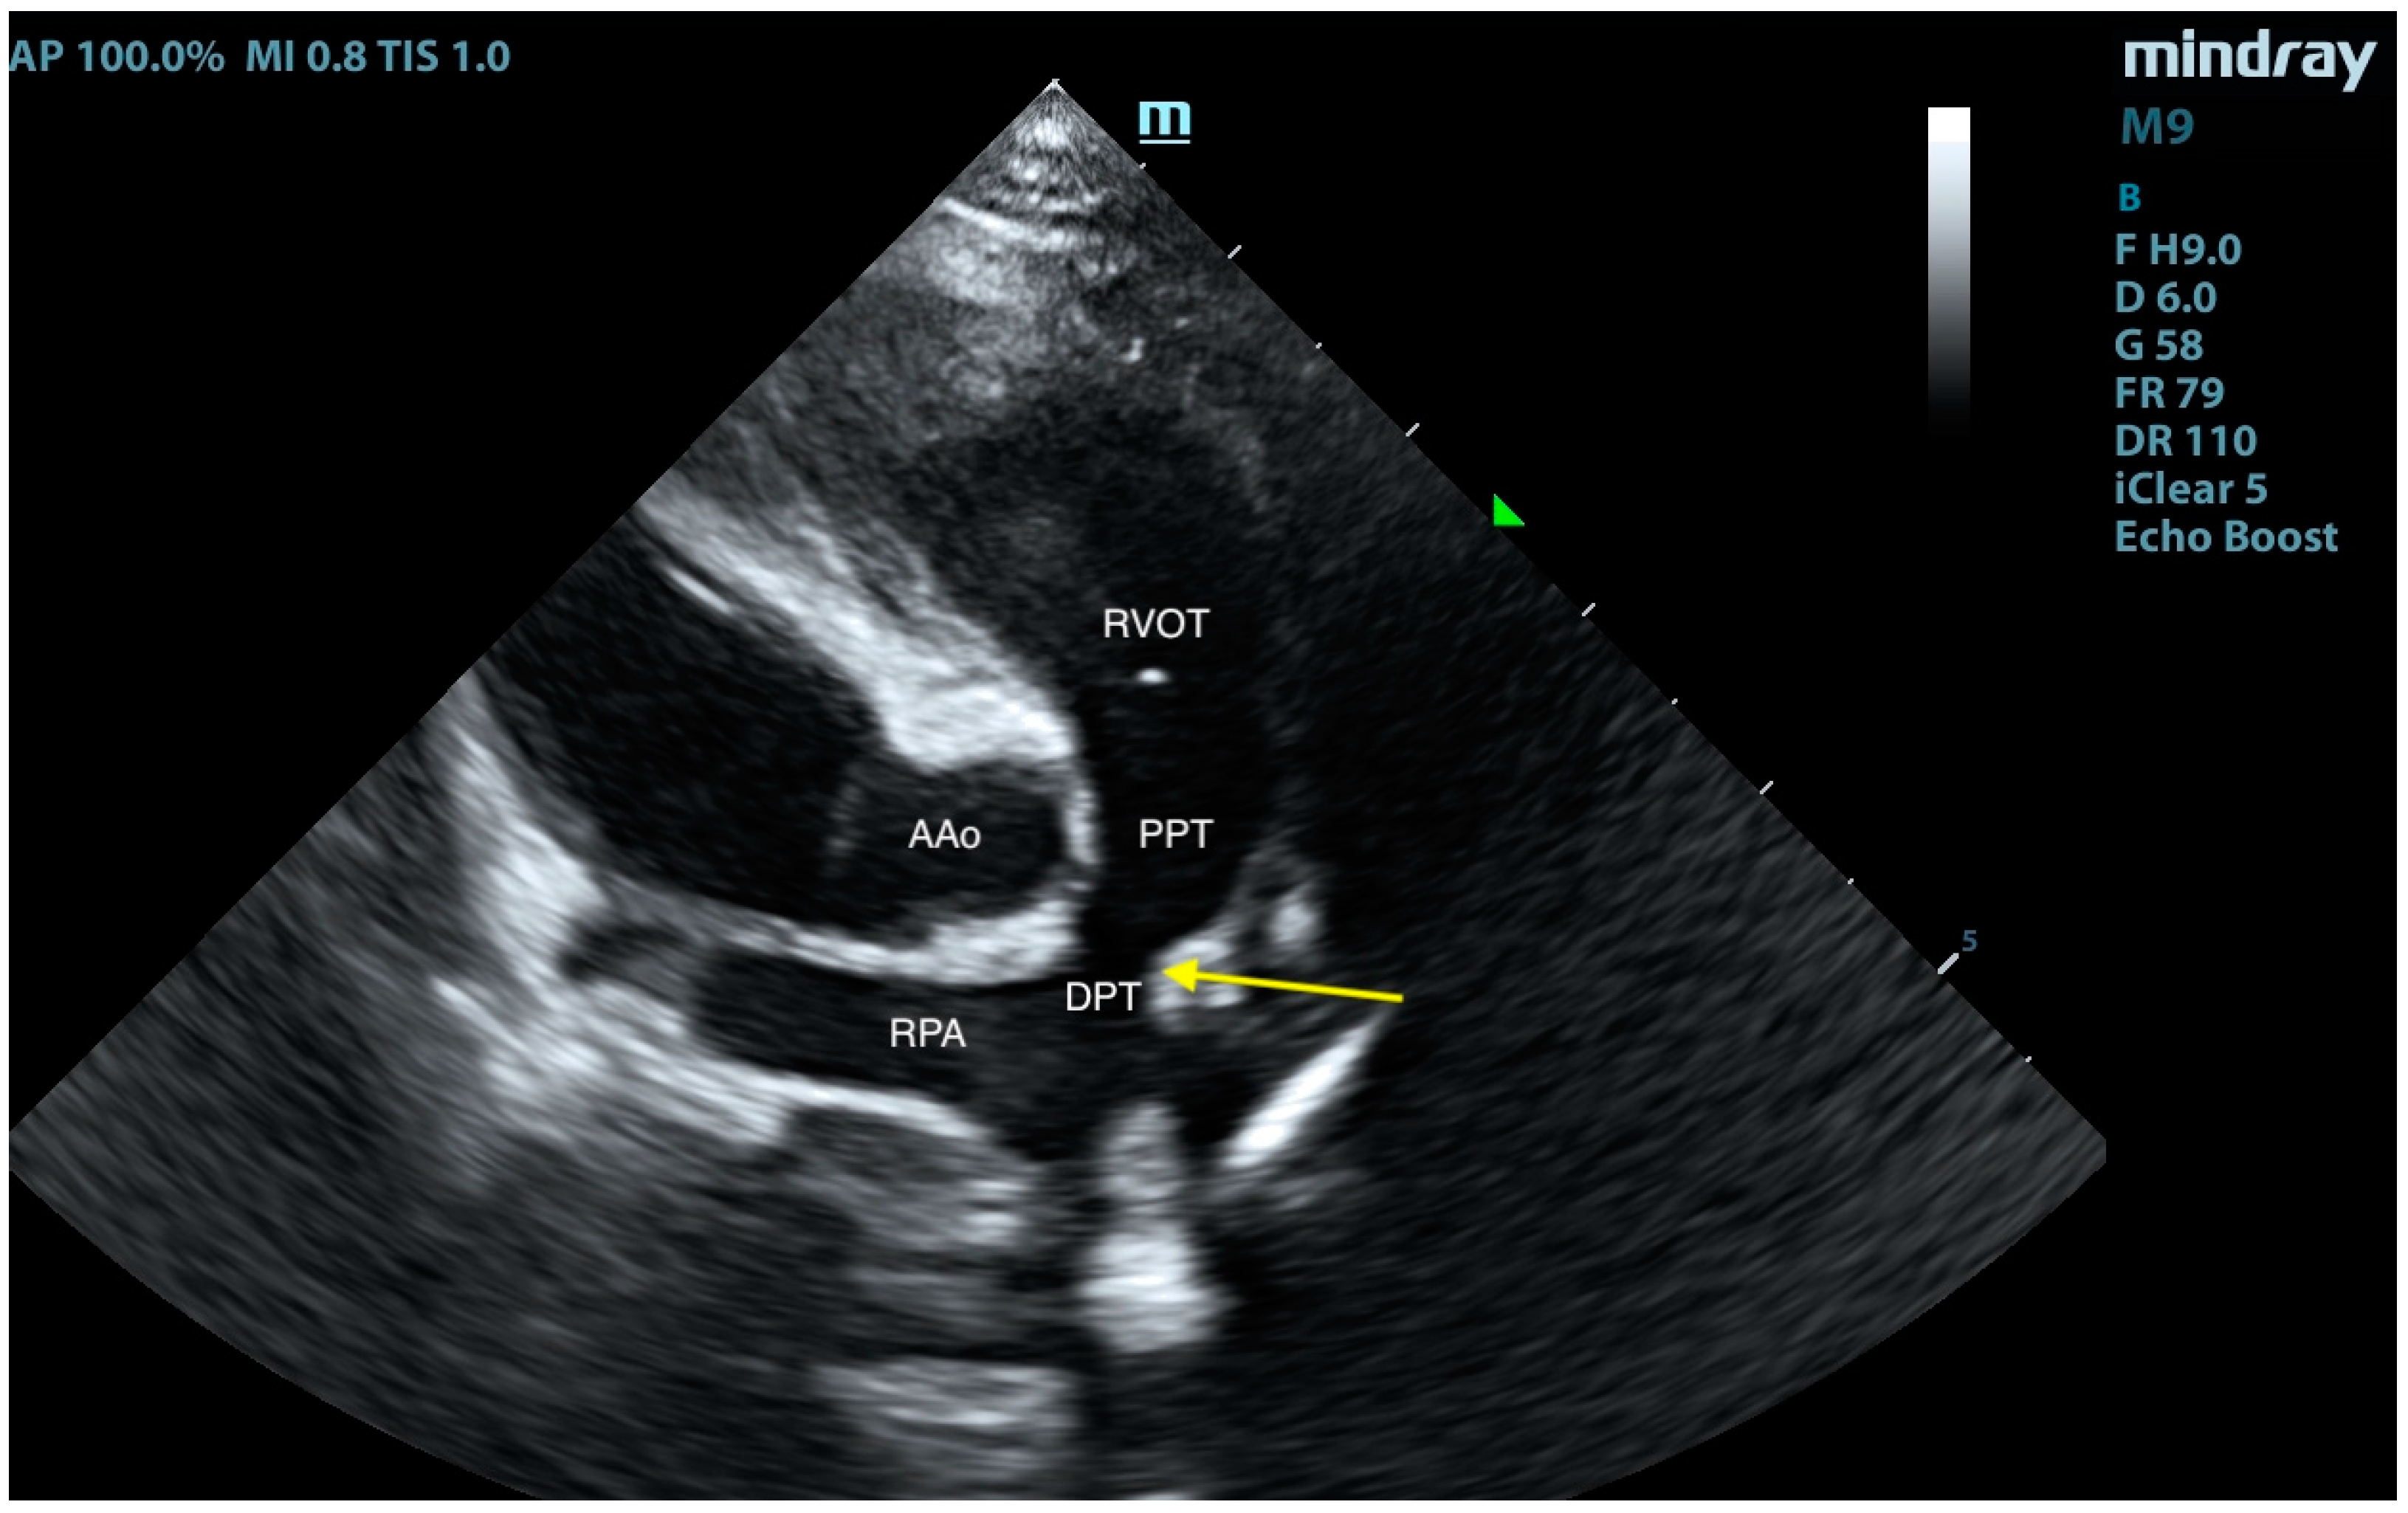

2. Case Presentation